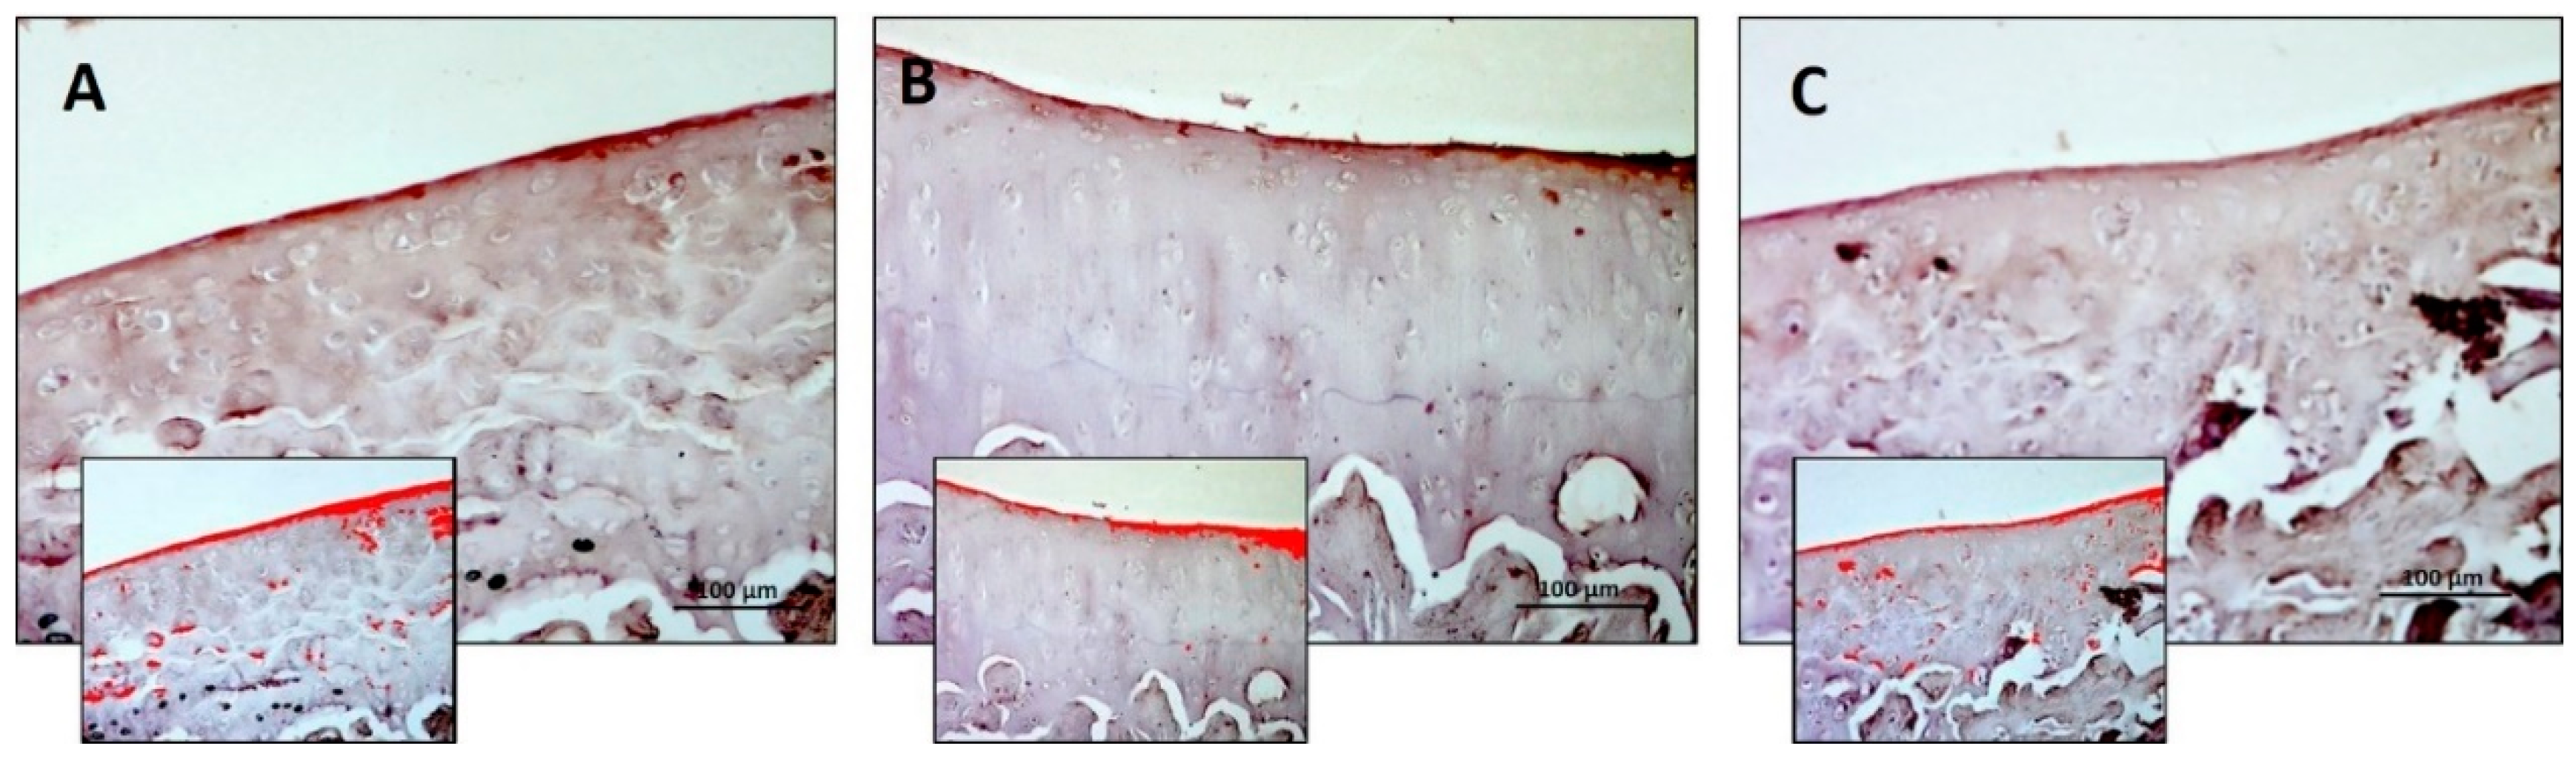

3.1. Histology and Histomorphometric Analysis

| Thickness (µm) | 235.7 ± 12.20 | 301.6 ± 19.25 | 130.00 ± 13.19 | R vs. R-DS: 0.0071 R vs. R-DR: < 0.0001 R-DS vs. R-DR: < 0.0001 |